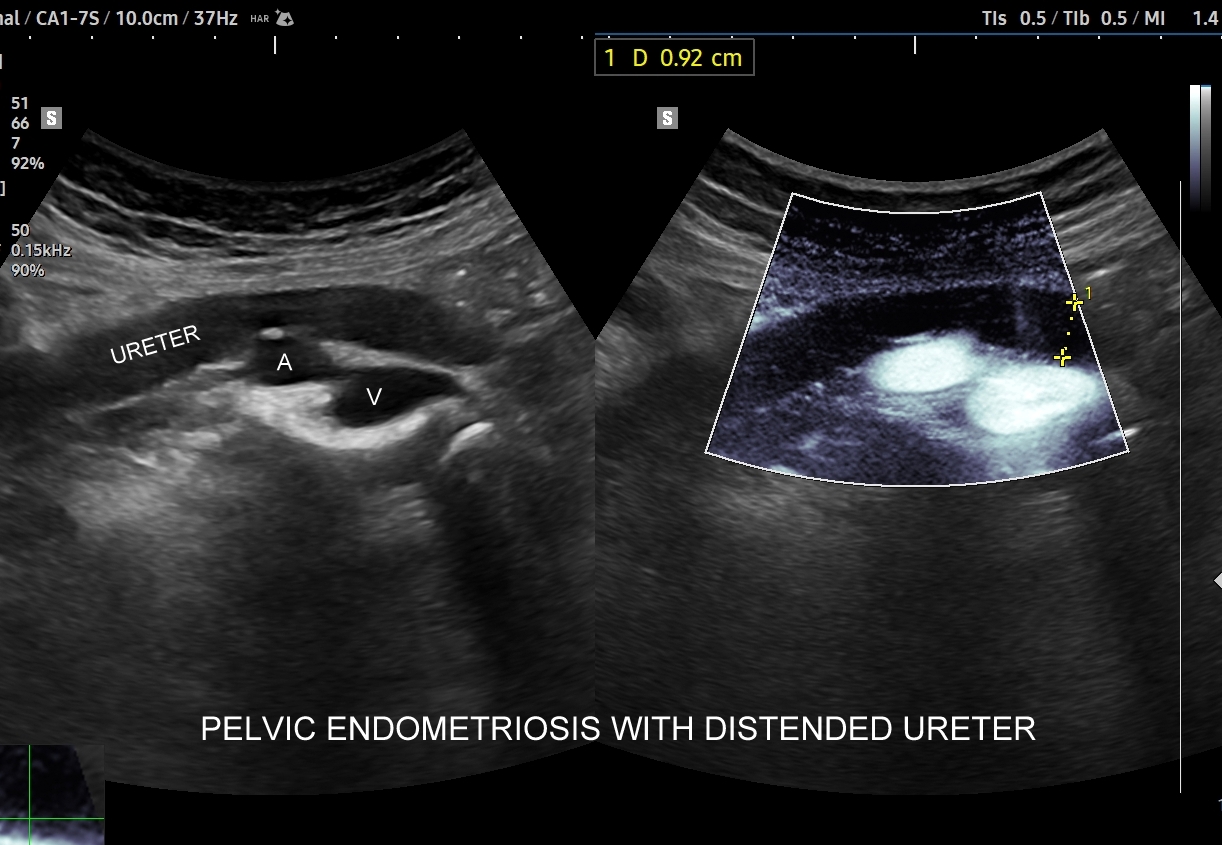

Endometrioza – metody diagnostyczne. Pierwszą linią diagnostyki endometriozy jest staranny wywiad oraz badania obrazowe w postaci USG transwaginalnego, USG przezbrzusznego oraz rezonansu magnetycznego MRI. Kombinowana czułość i specyficzność obu metod, tj. USG i MRI, sięga 90 %. Kolejnym etapem jest laparoskopia, która wykorzystywana jest zarówno jako procedura diagnostyczna, jak i lecznicza. W wyselekcjonowanych przypadkach endometriozy przydatne może być także badanie USG z kontrastem CEUS; np. do oceny zajęcia moczowodu.

Na skanach w niniejszym artykule zaprezentowany jest przypadek endometriozy głębokiej w miednicy mniejszej z intraluminalnym nacieczeniem dystalnego odcinka moczowodu, jego całkowitą niedrożnością i wtórnym wodonerczem. Choroba w tak zaawansowanym stadium wykryta została przypadkowo w rutynowym przezbrzusznym badaniu USG jamy brzusznej. W ramach diagnostyki różnicowej przeprowadzone zostały badanie CT, MRI oraz ureterocystoskopia z pobraniem materiału do badania histopatologicznego, na podstawie którego postawiono rozpoznanie endometriozy.